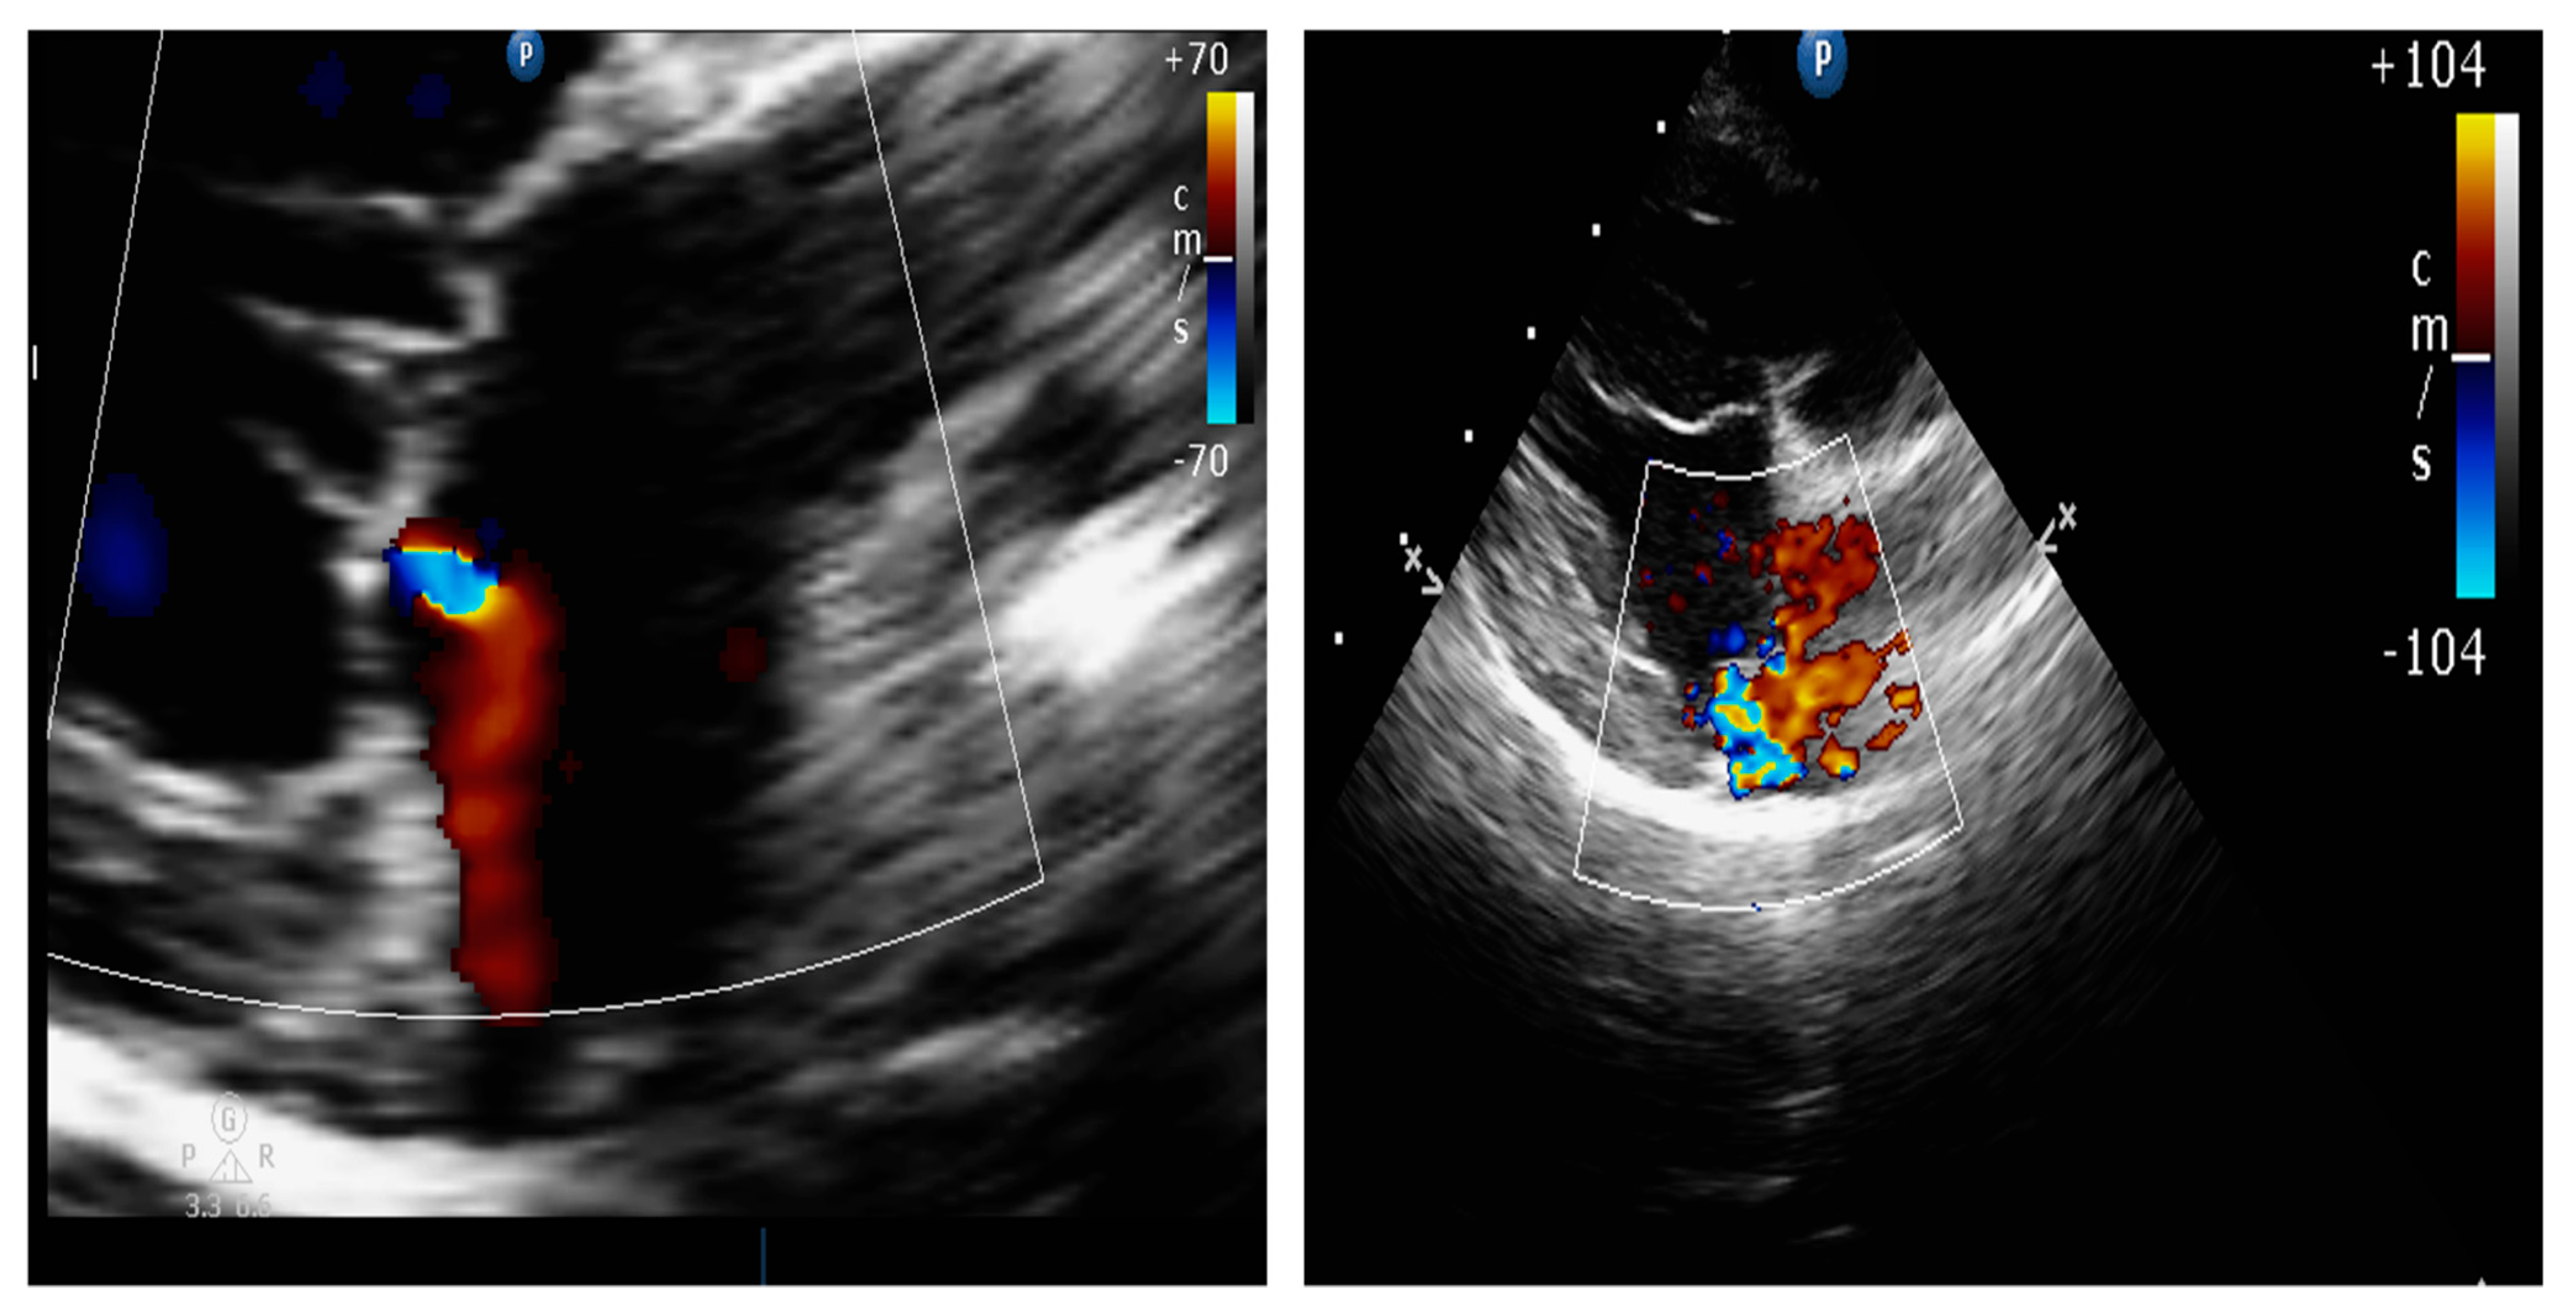

4.8.1. Evaluation of the Regurgitant Area

4.8.2. Presence of Vena Contracta

| Color flow imaging of the mitral regurgitation jet area | The most commonly used technique for assessing severity in dogs. The former method is not used in humans as it is not considered reliable for determining the severity of mitral insufficiency. |